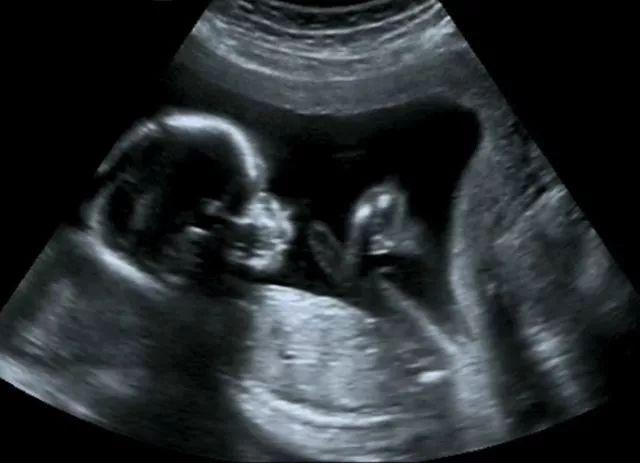

1.怀孕6周B超观察宝宝的发育情况,检查有无胎芽及胎心。

2.孕11-13周的NT 也是必不可少的,可以排除一些先天性疾病。

4.大排畸是对胎儿的系统结构性筛查,一般在孕21周 到24周之前。因为这个时间段胎儿的各个系统发育基本完成。通常这个时候排畸比较合适。这个时候胎儿的大小及羊水量也比较适合大排畸,对各个系统的结构及心脏看得特别清楚。